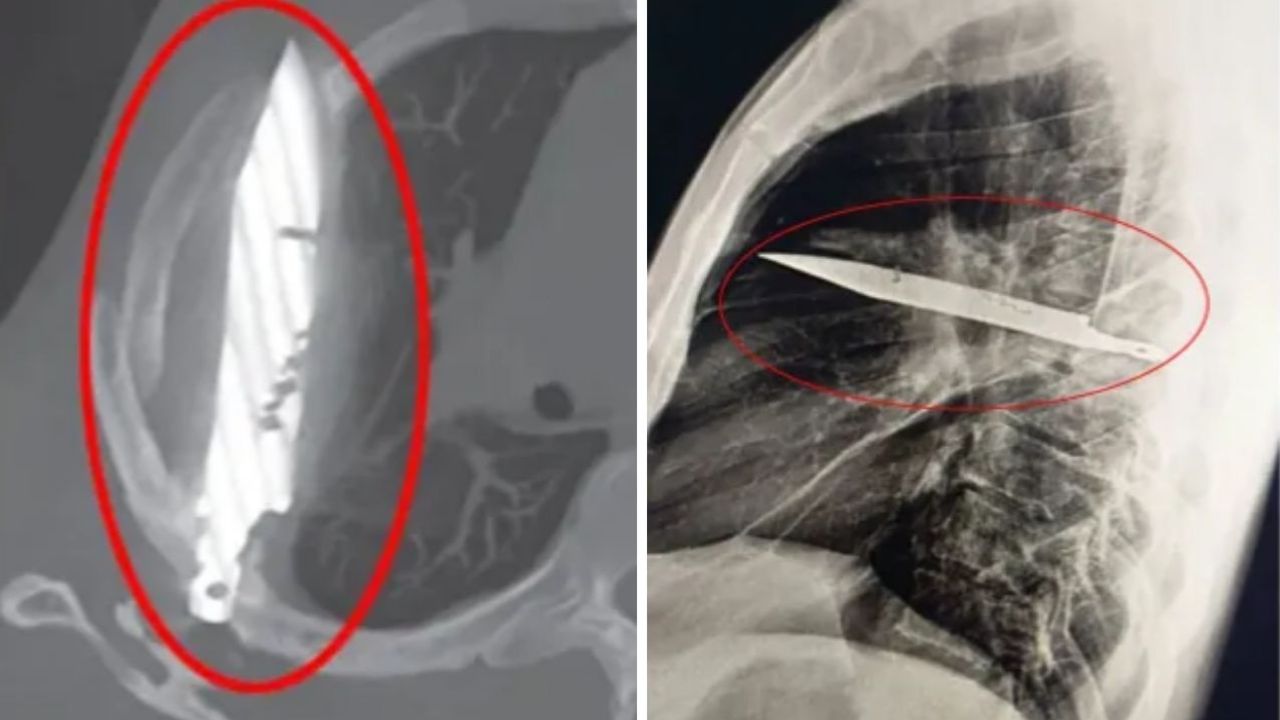

Röntgende adamın göğsünde saplı duran bir bıçak olduğu görüldü. Bunun üzerine açıklamalarda bulunan hasta, yaklaşık 8 yıl önce karıştığı bir kavga sırasında yüzünden, sırtından, göğsünden ve karnından yaralandığını, o zaman tedavi gördüğünü, ancak bıçağın saplandığını fark etmediklerini söyledi. O günden bu yana ciddi bir sağlık sorunu yaşamadığını söyleyen adam, gördükleri karşısında şaşkına döndü.

The Sun’ın haberine göre, sağ kürek kemiğinden girip hayati organlara zarar vermeden göğüste saplı kalan bıçak, acil ameliyatla alındı.